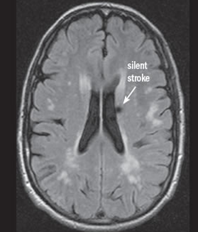

Deși unele tipuri de infarct sunt aparente pentru ochiul liber neprofesionist (Fig.2), altele sunt mai subtile și mult mai reduse în intensitatea aparentă și dimensiune (Fig.3 & Fig.4).

În imaginile din figurile 2-4 se pot vedea cu ochiul liber abnormalitățile la nivelul creierului din imaginile RMN. Astfel de cazuri reprezintă o parte importantă din setul de date, iar restul imaginilor e compus din cazuri mult mai greu de identificat sau clasificat chiar și pentru radiologii cu experiență. Pentru moment suntem departe de a concura cu precizia și acuratețea radiologilor, dar soluțiile de detecție automată de astfel de leziuni vor să vină în ajutorul medicilor. Un medic radiolog interpreta în jur de 679 imagini de tip RMN per zi în anul 2010 [9]. De atunci cantitatea de imagini produse de aparatura medicală e în continuă creștere iar presiunea asupra radiologilor crește și ea, iar cu aceasta cresc și șansele de eroare sau de ratare a unor leziuni importante. O soluție automată vine ca un adjuvant pentru radiolog asigurându-se că acestuia nu îi scapă niciun caz clar de leziune, iar radiologul se poate axa pe cazurile cu adevărat dificile și importante. Și în plus, un algoritm nu suferă de oboseală și nici nu necesită repaus.

Fig. 2 a) Simulare detecție de infarct cerebral acut din RMN-DWI. Ref: [6]

Fig. 3 Simulare detecție de infarct cerebral lacunar acut din RMN-DWI. Ref: [7]

Fig. 4 SImulare de detecție infarct cerebral din RMN-DWI. Ref: [8]